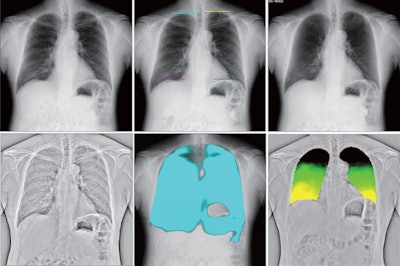

Several dynamic images obtained by DCR. Original DCR (A) is a simple dynamic image; diaphragm motion tracking processing mode (DM-mode) (B) emphasizes the movement of the diaphragm; bone suppression processing mode (BS-mode) (C) has the clavicle and ribs erased; and frequency enhancement processing mode (FE-mode) (D) enhances the visibility of the lung marking. Reference frame ratio calculation processing mode (PL-mode) (E) and lung motion tracking processing mode (LM-mode) (F) concern ventilation. PL-mode shows the dynamic ventilation image, demonstrating a blue shadow in the position where the lung tissue is expanded by breathing. LM mode visualizes upward movement of the lungs during expiration. The colorless area shows where there is little movement. Image and caption courtesy of the Journal of Thoracic Disease through CC BY 4.0.Dynamic image data were acquired at 15 frames per second and were synchronized with pulsed x-ray, with a radiation dose of approximately 1.7 mGy (under the 1.9 mGy dose limit for 2-directional chest x-rays recommended by the International Atomic Energy Agency, the authors noted).